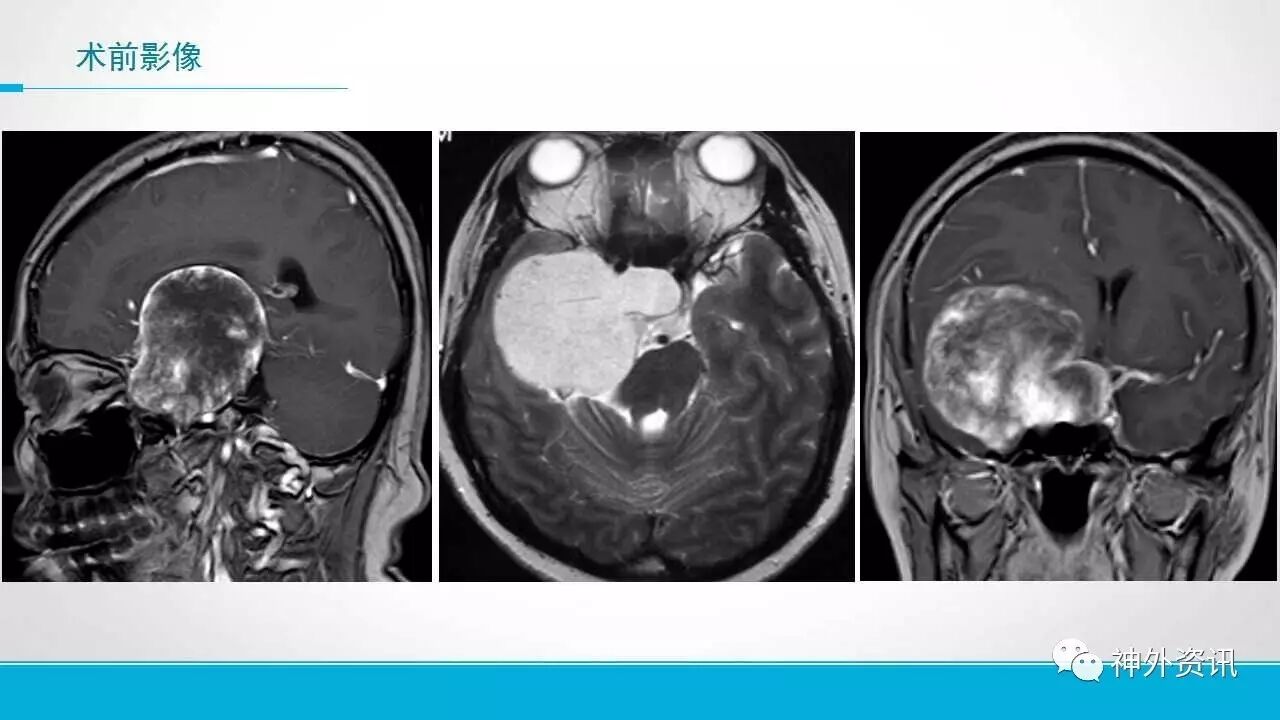

为大家分享的是《正海-妙术视界》第五十一期,由上海长征医院神经外科副主任陈菊祥教授带来的“Dolenc入路治疗海绵窦巨大海绵状血管瘤”手术视频及PPT,内容非常精彩,欢迎观看与分享。